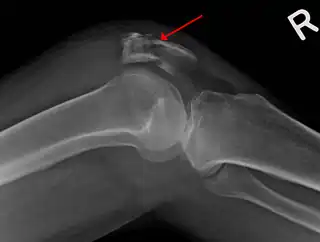

![]() Una fractura de la rótula vista en una vista lateral. | ||